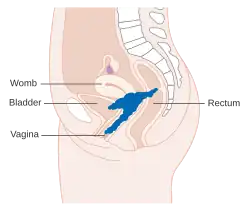

Stage 4A cervical cancer

Stage 4A cervical cancer -

Stage 4B cervical cancer

Stage 4B cervical cancer

The prognosis depends on the stage of the cancer. The prognosis for squamous cell carcinoma and adenocarcinoma of the cervix is the same for each given stage.[19] For intraepithelial cervical neoplasms, the prognosis is good.[129] With treatment, the five-year survival rate for FIGO stage 1 (cancer confined to the cervix) cervical cancer is 85%, and the overall (all stages combined) five-year survival rate is about 66%.[19][130] Five-year survival in Stage 2 disease (cancer invading beyond upper two-thirds of uterus) is 65%.[19] Stage 3 disease (in which the lower one-third of vagina, pelvic wall is involved or presence of hydronephrosis, pelvic or peri-aortic lymph node involvement) is 35%. Stage 4 disease, in which cancer extends beyond the pelvis, or involves the bladder or rectum, has a 5-year survival rate of 7%.[19]